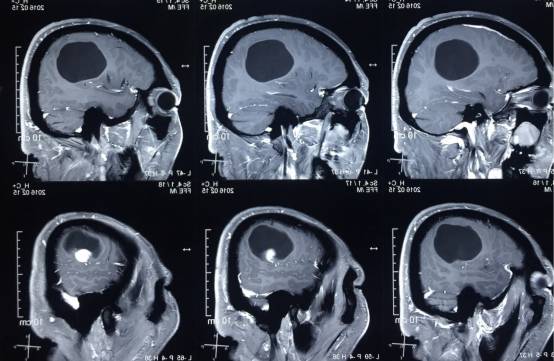

头颅MR示:右颞顶囊性占位伴结节,考虑胶质瘤可能。MRI T1为等信号(图1);T2囊液为高信号(图2);结节为均匀增强(图3);弥散相显示弥散受限(图4)。

图3. 结节为均匀增强。

术后患者恢复良好,神志清,精神佳,四肢肌力V级,肌张力正常,病理征(-)。术后CT(图5)MRI(图6)未见血肿,肿瘤全切。

图6. 术后48 小时 MRI (增强)。

PXA在CT平扫时表现为低密度囊性病变,境界多较清楚;附壁结节呈稍低密度或等密度,壁结节常紧邻软脑膜;囊性区因含有蛋白或出血,在CT上为略高于脑脊液的液性密度。在MRI上T1W1囊性区呈低信号,壁结节为低或等信号,T2W1为囊性区呈高信号,壁结节为稍高信号。增强扫描可见肿瘤附壁结节明显强化,囊壁可轻度强化或不强化,囊壁强化代表囊壁为肿瘤组织,囊壁不强化说明囊壁为反应性增生的胶质细胞构成。影像学典型表现为囊性病变伴壁结节,少数呈囊实性病变,钙化少见。充分认识这些影像特征有助于提高其诊断及鉴别诊断的准确性,为临床治疗及对预后的判断提供重要的参考价值。少数PXA表现不典型,呈囊实性病变,表现为密度或信号不均匀,增强扫描呈不均匀强化。